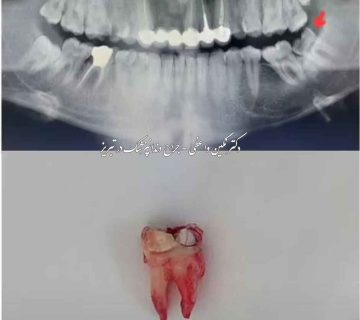

در این نمونه درمان انجام شده، عکس قبل و بعد کشیدن دندان عقل رو بدون درد و بخیه مشاهده می کنید.بیمار با شکایت درد و فشار روی لثه در هنگام غذا خوردن به مطب دکتر نگین واعظی مراجعه کردند. برای بیمار رادیوگرافی پانورامیک (OPG) تجویز شد و پس از آن طی بی حسی موضعی و بدون درد و جراحی ، دندان عقل بالا راست بیمار کشیده شد. در ادامه شما می توانید رادیوگرافی و عکس دندان عقل خارج شده رو مشاهده کنید.

عکس قبل و بعد کشیدن دندان عقل بالا

عکس رادیوگرافی پانورامیک قبل از کشیدن

تصویر دندان عقل کشیده شده